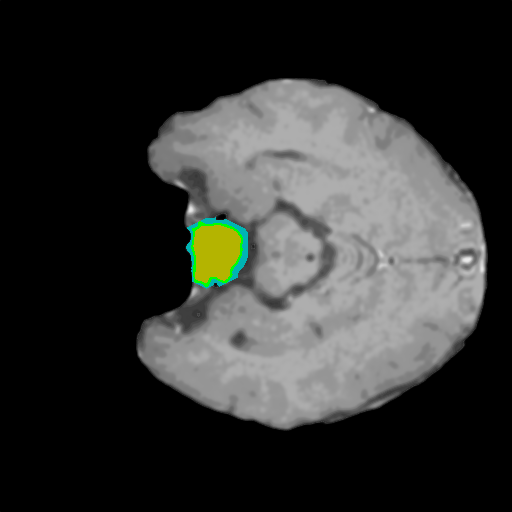

Extensive experiments have been performed in the current setup, and experimental outcomes are reported with the demonstration of numerical and statistical analyses using the proposed QFS-Net, QIS-Net [39], convolutional U-Net [18] and Residual U-Net (URes-Net) architectures [20]. The human expert segmented skull-tripped contrast enhanced DSC brain MR input image slices of size and ROIs are provided in Figure 5 as samples. The demonstration of QFS-Net segmented images followed by the essential post-processed outcome on the slice no. for class level with four distinct activation schemes () are shown in Figure 6. It is evident from the experimental data provided in Table LABEL:tab1 that the proposed QFS-Net performs optimally for the -connected quantum fuzzy pixel information heterogeneity assisted activation () with and gray scale set in comparison with other thresholding schemes and gray scale sets under the four evaluation parameters () [44]. The segmented tumors obtained using the proposed self-supervised procedure under class transition levels with four different thresholding schemes , , and are demonstrated in Figures 7- 8 for the class boundary sets and [39], respectively. The segmented images using the remaining two class boundary sets ( and ) [39] are provided in the supplementary materials section. The segmented ROIs describing the whole tumor region after the masking procedure using QIS-Net, U-Net and URes-Net are also reported in Figure 9.